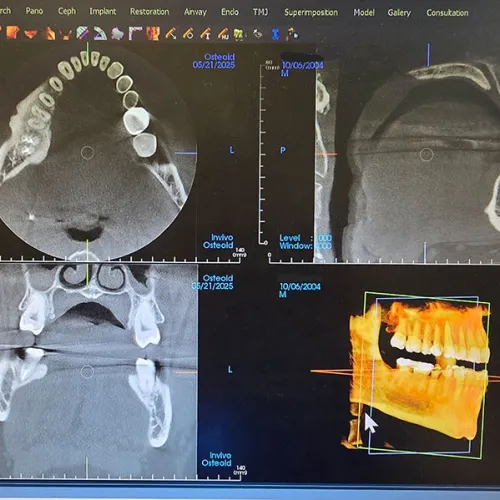

Dental 3D CT scan showing jawbone, teeth alignment, and implant planning with restoration and airway analysis.

CBCT 3-D Scanning

Our 3-D scanning shows a complete picture of what's happening beneath the surface of your smile. It gives us a detailed, 3-D view of your teeth, jaw, and bone. It's essential for planning complex procedures.

What is a CBCT scan, and why would I need one?

CBCT stands for cone beam computed tomography. It's a type of 3-D imaging that gives us a detailed view of your teeth, jawbone, sinuses, and nerves. We typically use it for more advanced treatment planning, as the scan is quick, non-invasive, and provides exact dimensions and structures. That means safer, more predictable results.